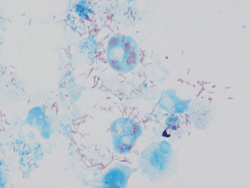

Rickettsia conorii observed in Vero cells (red rods; magnification ×1,000)[1] | |